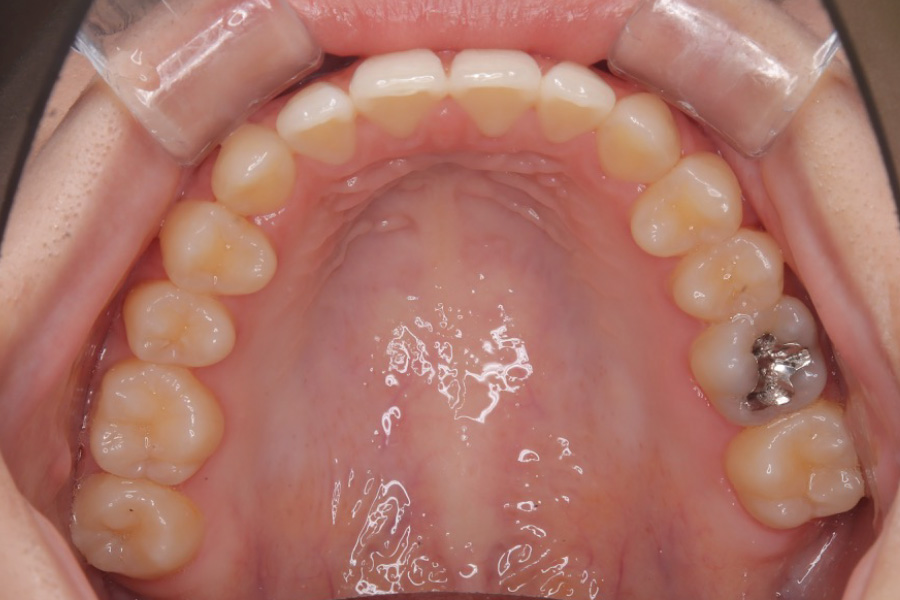

治療後

主訴 前歯で噛めない

治療内容 インビザライン矯正

非抜歯